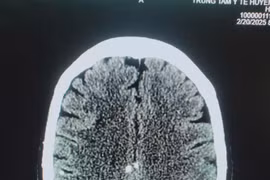

Mới đây, Trung tâm y tế huyện Thanh Sơn (Phú Thọ) đã tiếp nhận người bệnh Đ.V.C. (66 tuổi, trú tại xã Thượng Cửu, huyện Thanh Sơn) trong tình trạng cổ to bất thường, kèm theo chóng mặt, đau đầu.

Người bệnh Hà Văn K (60 tuổi), tại huyện Thanh Sơn thường xuyên ăn tiết canh, rau sống… Khi bị đau đầu, liệt nửa người phải nhập viện thì được chẩn đoán mắc đa nang kén sán não.

Có thói quen ăn tiết canh để giải nhiệt và "giải đen", ông L.V.B (68 tuổi, ở Thanh Hóa) thường xuyên đau đầu, co giật, sùi bọt mép, đi khám bất ngờ phát hiện tổ sán chi chít trong não.

Kết quả chụp CT não cho thấy có 5 ổ sán nằm rải rác trong não, trong đó có một ổ sán lớn trên đỉnh đầu của bệnh nhân gây phù não. Bệnh nhân được chỉ định phẫu thuật gấp.